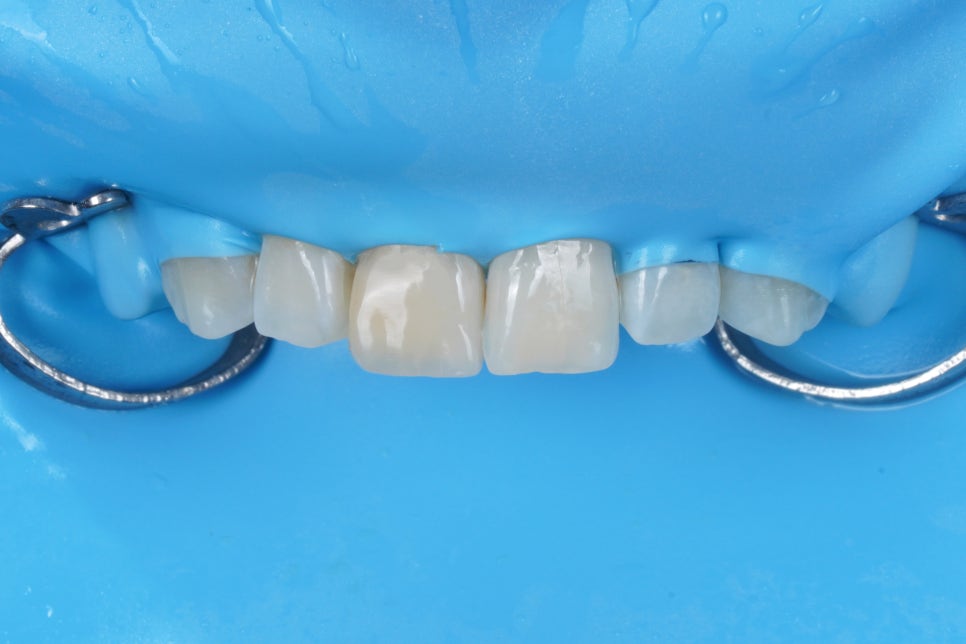

이렇게

<러버댐>이라는 재료를 이용해서

때울 부위를 구강내와 격리하는

사전작업이 필요한 이유입니다.

침과 피, 구강내 습기로부터

격리되지 않은 부위는

언제든 이렇게 오염될 수 있습니다.

세라믹도 결국에는

레진으로 치아에 부착하기 때문에

세라믹과 치아 사이에

샌드위치처럼 끼워진 Resin이

결국 변색되기 때문입니다.

대부분 방습이 안된 상태에서

세라믹 라미네이트를 Resin으로 접착하기때문에

어떤면에서는 러버댐 방습하에서

Resin 단일 재료로 복원하는 것이

더 우수한 장기 안정성을 가져오기도 합니다.